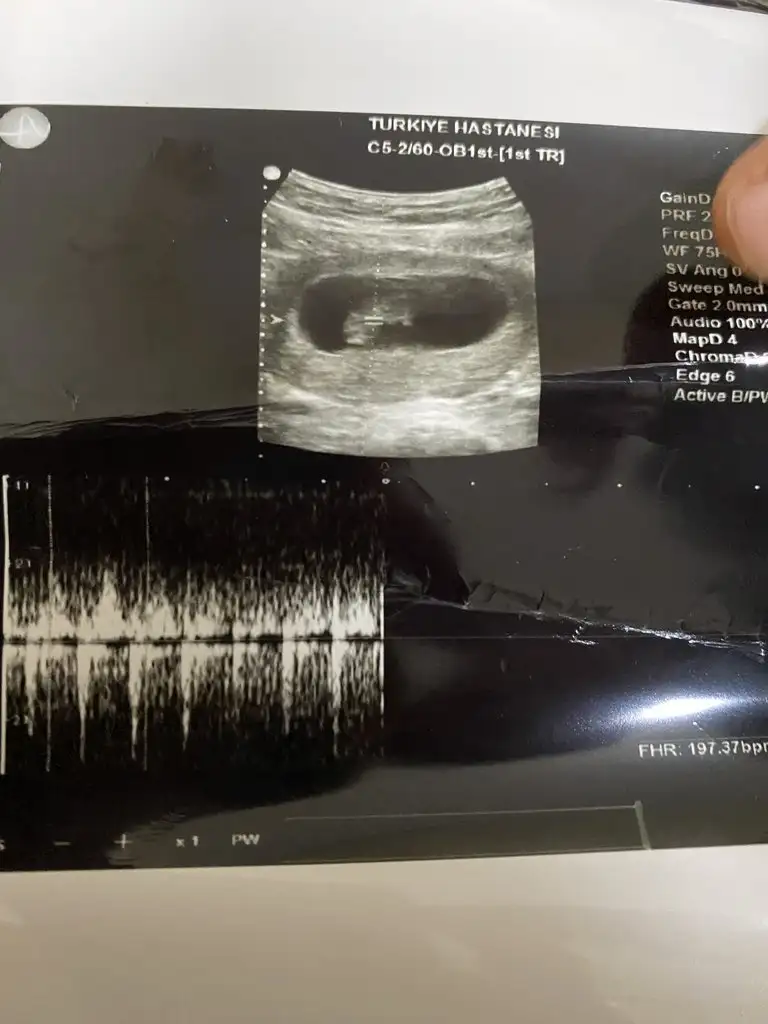

Bugune kdr hep ben sizinkini yorumladım simdide sıra sizde ablalarım ben daha minnagım 6+4 üz sata göre ama dr ablamız 6+2 dedi 🙏🏻 Saglıklı olsun tek duamız . Ama Eşim kız bebek istiyor sizce ? Kocaman kese açmış kendine bu dedi dr

16063F0C-0BA9-41B5-B389-3907C8209F98.webp